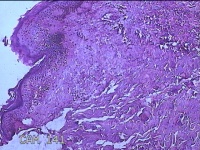

左大腿皮肤肿物

性别

男

年龄

34岁

临床诊断

皮肤感染

一般病史

左大腿麻木十五年。

标本名称

大体所见

灰白粉红色肿物0.7x0.5x0.2cm一个,表面糜烂。

图1